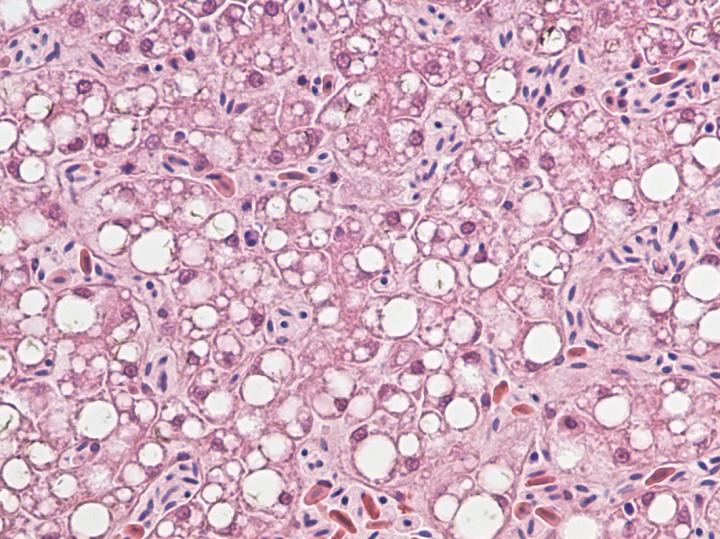

Officials at the USGS National Wildlife Health Center conducted necropsies to determine the cause of death and found liver damage in most of the birds. Damage to brain tissue was also common. Searches for environmental toxins underlying the disease came up empty.

Working with White and Strom, Goldberg's lab analyzed liver tissue from nine birds diagnosed with WRES. The team first spotted the new virus in a bald eagle collected in 2002 in Sauk County. This family of viruses had not been found in birds before, although it has since been identified in ducks as well.

"It is curious that the liver pathology of the eagles resembles the damage to human livers caused by hepaciviruses," says White, branch chief for wildlife epidemiology and emerging diseases at the USGS National Wildlife Health Center. "But since the lesions are nonspecific there's more that needs to be explored if we want to understand the virus itself or really get at what is the cause of WRES."